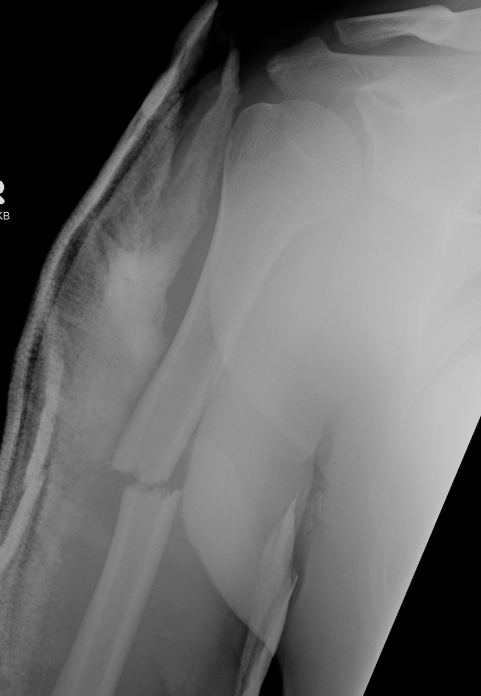

Medial Epicondyle / Condyle Fracture

Medial Epicondyle

Aetiology

Dislocation

Dislocation

2 groups

1. Elderly

- low velocity injury

- osteoporotic

- need to start bisphosphonates

2. Young patients

- high velocity injury

Usually a direct blow

- less commonly a fall on the outstretched hand

RTA / sporting accidents commonest causes